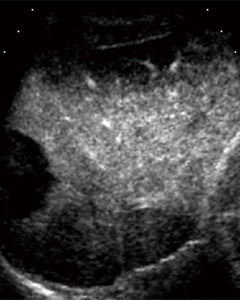

図5 US contrast像を取り込んだRVS (画像ご提供:岡山大学 小林功幸先生)

a:焼灼後のUS contrast像 (バーチャル像)

b:B像 (リアルタイム像)